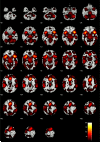

Methods: This study examined the impact of a placebo [breath alcohol concentration (BrAC) = 0.00%], moderate (BrAC = 0.05%), and high (BrAC = 0.10%) doses of alcohol on brain hemodynamic activity during a functional MRI (fMRI) Go/No-Go task in 38 healthy volunteers.

Results: Alcohol increased reaction time and false alarm errors in a dose-dependent manner. fMRI analyses showed alcohol decreased activity in anterior cingulate, lateral prefrontal cortex, insula, and parietal lobe regions during false alarm responses to No-Go stimuli.